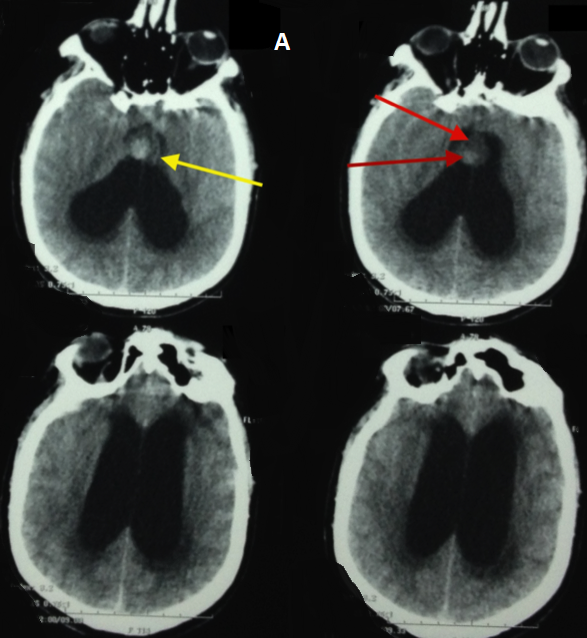

Bruns syndrome was first described in 1902, as a sudden onset of severe headaches and vomiting associated to a vestibular syndrome provoked by abrupt change in head position. It is related to an episodic obstructive hydrocephalous caused by an intraventricular mass that acts like a ball-valve mechanism. A 52 years old man was admitted to the intensive care unit for a sudden onset coma. His Glasgow Coma Scale was 4/15 with fixed dilated pupils. He has been experiencing paroxystic episodes of headaches, vomiting and vertigo for 6 months that went undiagnosed.Diagnoses include acute hydrocephalous, syncopes, and stroke. The CT scan showed a globally iso-dense rounded mass of the anterior roof of the third ventricle, with hyperdense areas suggestive of hemorrhage, obstructing both foramen of Monro and causing acute hydrocephalous. The patient underwent an urgent placement of an external ventricular drainage; the intracranial pressure was above 25mmHg, and the CSF gin-clear.Unfortunately, the patient did not survive this episode and died 24hours later. Colloid cysts are rare, benign, and curable lesions located at the anterior part of the roof of the third ventricle, and contain colloid material. Their clinical presentation varies from incidentally found cysts to sudden death.Rapid deterioration may also be caused by an intrinsic hemorrhage. Such condition has only been reported in the literature in 16 publications. Through this observation we would like to bring attention concerning this syndrome that may be preceding fulminant and lethal deterioration from a benign and surgically curable lesion.